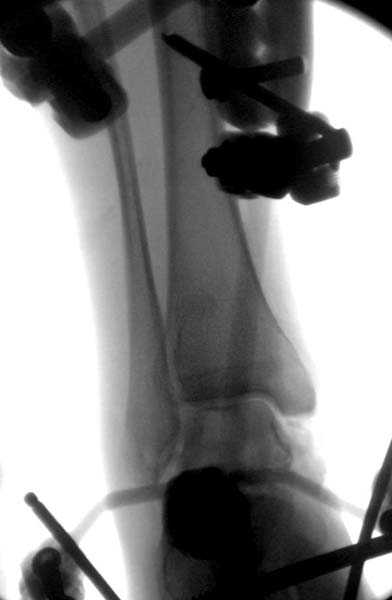

> Больная стабильная после хирургических мероприятии и получив добро,

> приступили к закрытому вправлению таранной кости с укладкой наружного

> фиксатора. Затем укладка больную на бок и открытый остеосинтез

> Остеосинтез бедра не стали делать из-за множественных переломов ребер с

> ушибом грудной клетки и поэтом у закончили фиксацию бедра наружным

> фиксатором.